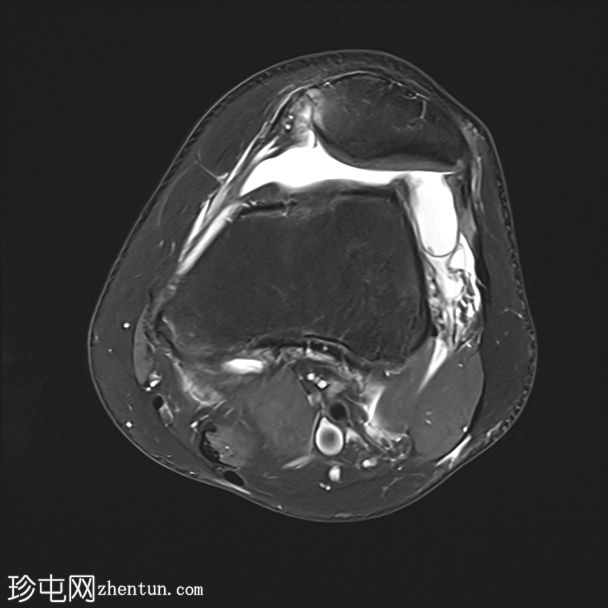

冠状位PD序列

脂肪抑制序列

内侧髌股韧带撕裂,伴外侧髌骨半脱位。

内侧髌骨缘可见骨髓水肿和一小块皮质撕脱碎片,内侧髌骨关节面存在全层软骨缺损。

外侧股骨髁轻度骨髓水肿。

内侧副韧带和外侧副韧带II级损伤。

膝关节积液

这些影像学表现是滑车发育不良的典型特征,滑车发育不良是髌骨不稳定的最常见病因,尤其是复发性髌骨外侧脱位。